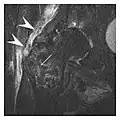

Proximal femoral fractures usually occur in osteoporotic patients, and their signs include subtle neck angulation, trabecular angulation, and subcapital impaction line. A frog-leg lateral view may be helpful if the greater trochanter is short enough. However, positioning can be difficult because of hip pain. In patients with strong suspicion of proximal femoral fracture and negative radiographs, MRI limited to coronal T1 W images and scintigraphy can be highly valuable (Figures 13 and 14). Such an option, with limited examination time, is cost-effective and allows reliable exclusion or confirmation of the diagnosis, preventing an unnecessary stay at the hospital or delayed treatment. Moreover, MRI helps to detect soft tissue abnormalities which are more frequently seen in femoral, acetabular, and pubic injuries than sacral lesions. Concomitant fractures are also frequently seen in typical pelvic sites.[1]

a

b

Figure 13: Partial osseous avulsion of the gluteal muscles at the greater trochanter in a 59-year-old man who presented with the right hip pain without a history of trauma. Lauenstein view and anteroposterior and radiographs (not shown) did not show an obvious fracture line or disruption of bony contours in the acetabulum or the right femoral neck. (a) Coronal T1-weighted MRI displays an incomplete fracture line extending partially from the greater trochanter (arrow). (b) Coronal short tau inversion recovery MRI shows heterogeneous hyperintensity in the same region (arrow) as well as hyperintensity within the gluteus medius and minimus muscles (arrowheads) consistent with tissue edema and hematoma.[1]

Figure 14: Subcapital insufficiency fracture in a 55-year-old man with a left hip pain without a history of trauma. Anteroposterior and Lauenstein view radiographs centered on the left hip do not show an obvious fracture line, but mild acetabular osteophytosis was noted consistent with hip osteoarthritis (not shown). (a) Coronal T1-weighted MRI shows a linear low-signal band through the femoral neck corresponding to a fracture line (arrowheads). (b) Bone scintigraphy shows focal uptake (arrow) corresponding to the fracture.[1]